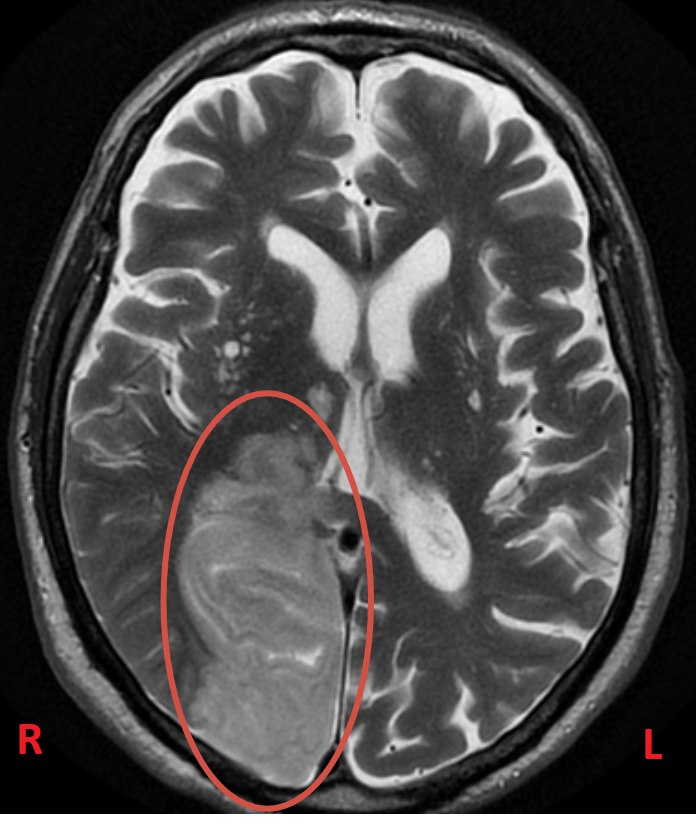

В нашем отделении уже через час была выполнена МРТ головного мозга, и диагноз подтвердился: острое нарушение мозгового кровообращения (инсульт).

В нашем случае МРТ показала инсульт в правой затылочной доле (в бассейне правой задней мозговой артерии).